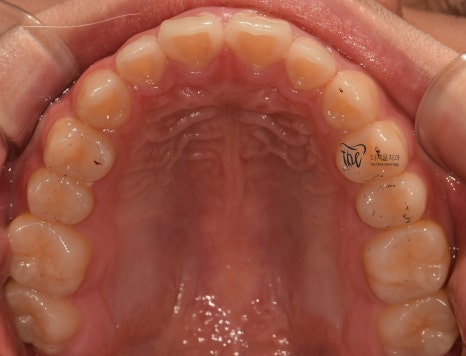

『초진 사진 및 진단 내용』

근데 또 교합면에서 보면, 악궁의 형태 자체는

그렇게 나쁜 편은 아닙니다. 다만, 회전이 되어있는

일부 치아들 및 치간이개의 현상 이외에는

별다른 특이사항을 볼 수 없죠.

교합면에서 봤을 때는, 거의 무턱 교정 치료가

다 끝난거와 같은 느낌을 받으실 수 있습니다.

원래, 악궁 자체는 그렇게 나쁜 편은

아니였기 때문에 크게 달라졌다고 느낌을

받기는 쉽지 않네요.

처음에 오셨을 때, 총생의 정도가 심했다면

전후 가 조금 더 명확했을 듯 합니다.